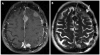

This article provides an overview of the neuroimaging literature focused on preoperative prediction of meningioma consistency. A validated, noninvasive neuroimaging method to predict tumor consistency can provide valuable information regarding neurosurgical planning and patient counseling. Most of the neuroimaging literature indicates conventional MRI using T2-weighted imaging may be helpful to predict meningioma consistency; however, further rigorous validation is necessary. Much less is known about advanced MRI techniques, such as diffusion MRI, MR elastography (MRE), and MR spectroscopy. Of these methods, MRE and diffusion tensor imaging appear particularly promising.